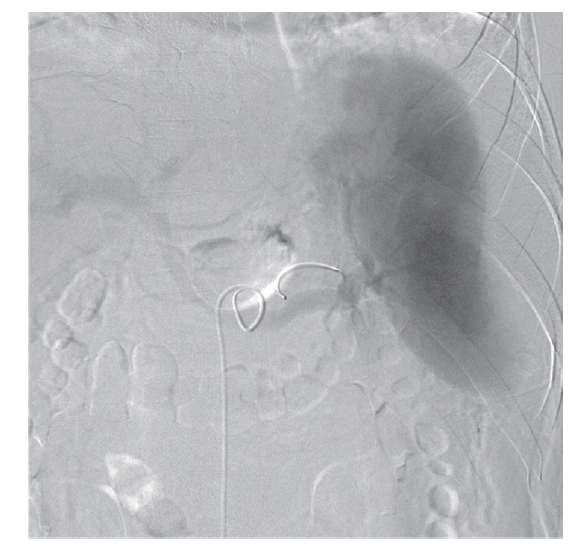

The patient’s hemoglobin level was 14.4 g/dl 1 day before visiting the Emergency Department and decreased to 11.0 g/dl. The concentration then rapidly dropped to 9.5 g/dl, and the patient received a blood transfusion. The patient also had thrombocytopenia (71 k/μl) with 33 IU/L AST, 44 IU/L ALT, 25.4 mg/dl BUN, and 1.66 mg/dl creatinine. He was admitted to the intensive care unit for a conservative treatment. Despite transfusion, the hemoglobin levels and blood pressure remained unstable. On the second day of hospitalization, a splenic angiogram was performed. No definitive extravasation of contrast media was observed, but contour irregularity was noted in the lateral lower margin (Fig. 3). Embolization was performed with 7 coils (10×4 mm, 8×4 mm, 6×2 mm; Cook, Bloomington, Minneapolis, USA) at the distal splenic artery level (Fig. 4).